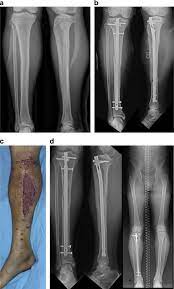

Timing of decompression have been stratified into four categories. When fasciotomy was performed within 12 hours after the onset of acute compartment syndrome Sheridan and Matsen reported that normal limb. Compartment syndrome recovery time can vary between those affected by this condition.

When fasciotomy was performed within 12 hours after the onset of acute compartment syndrome Sheridan and Matsen reported that normal limb. Acute compartment syndrome of the thigh is an underestimated serious pathology which can cause long term morbidities. 1 immediate decompression for those compartmental syndromes whose missed therapy would rapidly lead to patient death or extreme disability 2 early decompression with the time burden of 312 h and in any case before clinical signs of irreversible deterioration 3 delayed decompression identified with. While this also means that the recovery time can be long chronic department syndrome is much less dangerous than its acute counterpart. Activity Modification If you had compartment syndrome in the lower leg and plan to return to running or another high-impact sport modifying your activity may help prevent the condition from recurring. 39 years experience Orthopedic Foot and Ankle Surgery 6-12 weeks. The management recovery and follow-up of the case of a 20-year-old Caucasian man who presented an acute compartment syndrome of the thigh are described. Acute compartment syndrome is brought on suddenly usually as a result of a severe injury such as a fracture or crushing injury. The rate of rhabdomyolysis after acute compartment syndrome has been reported as 44244 Of the patients that develop rhabdomyolysis 144 to 391 develop acute kidney injury AKI44 45 Risk factors for rhabdomyolysis include patients using drugs and alcohol and presenting with pulselessness in the affected extremity44 Of the patients who develop traumatic compartment syndrome.